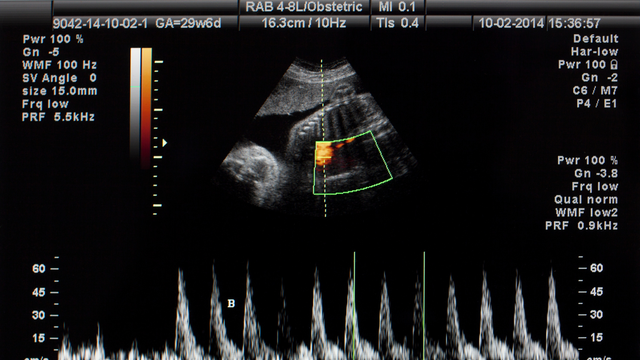

thai kỳ

Nhiều biến chứng thai kỳ nghiêm trọng có thể phòng được nhờ các mũi vắc xin phù hợp cho từng giai đoạn mang thai. Việc hiểu rõ mũi nào an toàn, mũi nào bắt buộc giúp mẹ bảo vệ cả mình lẫn em bé hiệu quả hơn.